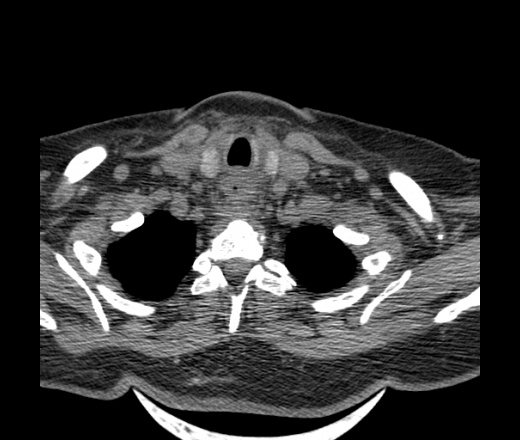

Женщина поступила в х/о спустя 4 дня после того как при употреблении карася подавилась костью.

Наличие газа в средостении на протяжении тел С2-С6 (медиастинальна эмфизема); рыбная кость на уровне тела С6.

При всем уважении, но говорить о медиастинальной эмфиземе, оценивая мягкие ткани шеи, как-то слишком резко. На мой взгляд, это ретрофарингеальное пространство.

Эвакуировали почти 100мл гноя. Но кость не смогли найти. Думаю что она даст дальнейшее ослоднение. Эндоскопически за черпалонадгортаной звязкой не смогли зайти в пищевод, все мягкие ткани отечные, просвет пищевода сдавлен. По всей видимости параэзофагеальная клетчака тоже задействована. Эмпиема, если ее можно так назвать, незнаю как правильно дошла до уровня яремной вырезки. Чем закончиться напишу. Ждем медиастинита.

Флегмона заглоточного пространства шеи, только операция, флегмоны вскрывают. Риск медиастинита.

Согласен с Вами; конечно, наличие газа в клетчатке ретрофарингеального пространства (затмение с опечаткой..). К сожалению, процесс "продвигается" к медиастиниту. Но почему никто, не отмечает наличие рыб. кости; или это для Всех очевидно?

Так вы уже отметили. Хотя ориентировал бы не скелетотопически, а на перстнечерпаловидный сустав.

Кость то мы сразу выявили, размеры где то 17*2мм, но ее так и не получается найти в этой каше